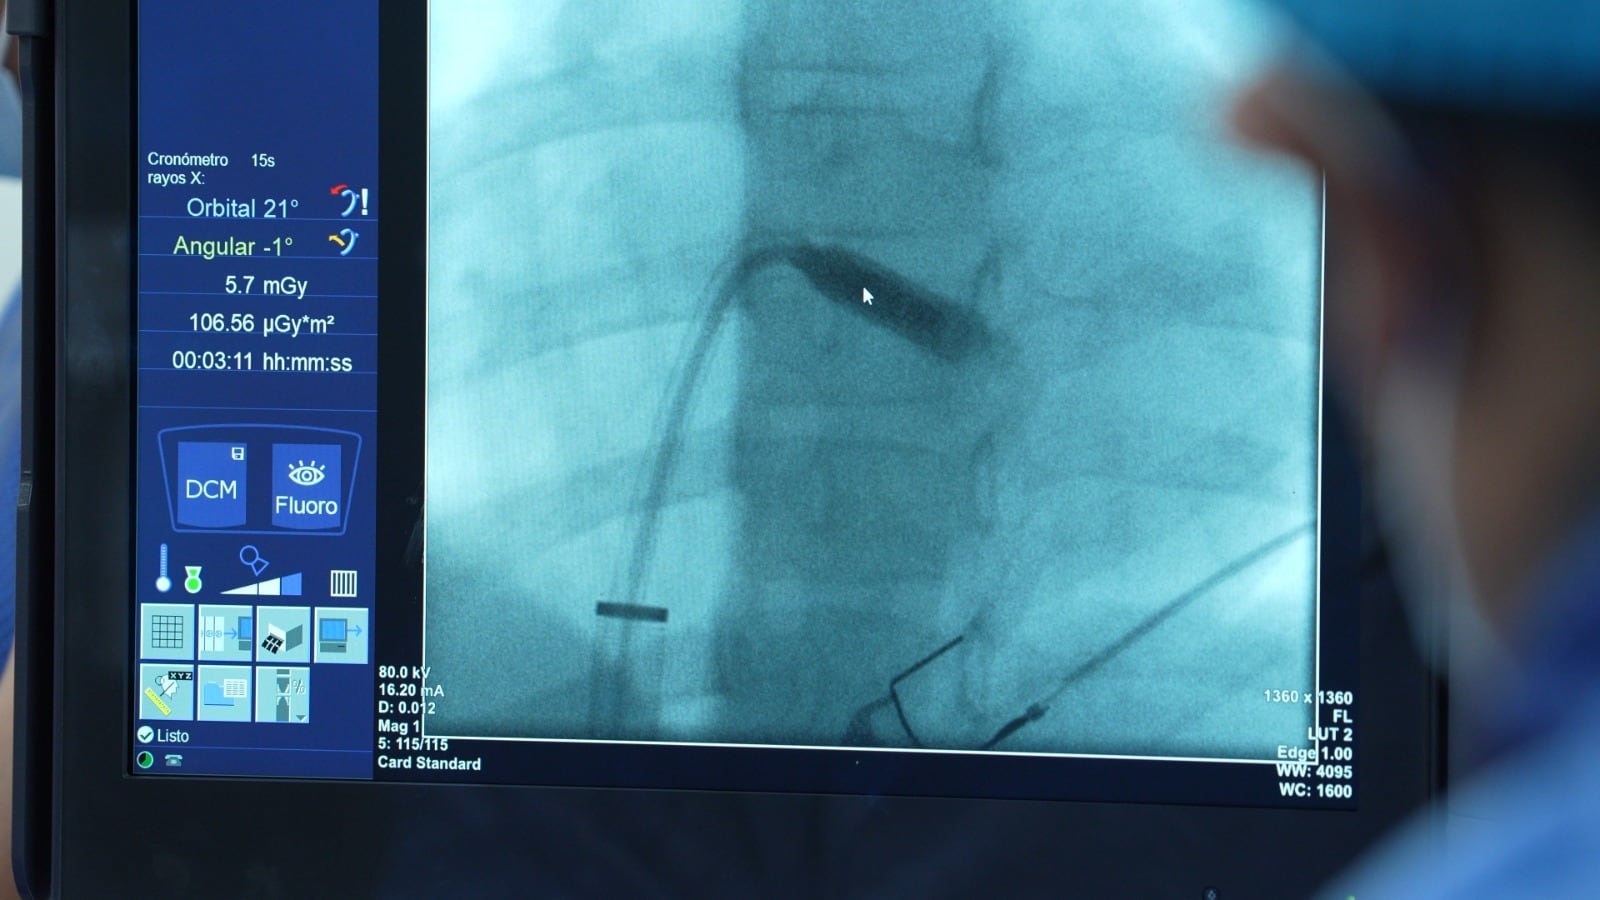

Fue entonces cuando la historia tomó un giro trascendental. No solo el Dr. Fontinier lideraría el caso, sino que se convocaría a un especialista estadounidense, pues se trataba del primer caso en el mundo de una niña de 9 años en recibir el marcapasos microchip más pequeño existente. El especialista en elecrofisiología y cardiología intervencionista de la clínica Good Hope tenía experiencia implantando estos dispositivos en adultos, pero en niños era una primicia.

Lo que se esperaba que durara entre una y tres horas, sorprendentemente, fue casi inmediato. “Duró unos minutos nada más”, recuerda Otilia con asombro. El Dr. Fontinier también se mostró impresionado por la eficiencia del procedimiento. “De los 13 que he realizado este ha sido el más sencillo. No sé por qué. Llámale Dios, llámale fortuna, experiencia, pero la punción fue muy limpia. Metí el catéter dentro del corazón, se posicionó donde debía posicionarse, lo solté, el marcapaso quedó muy bien y salimos. No nos demoramos 15 minutos en el procedimiento. ¡15 minutos!”, cuenta Fontinier todavía asombrado.

Un detalle técnico conmovió especialmente a los presentes: los marcapasos suelen tener cuatro pequeños ganchos para sujetarse al corazón, y con que dos se conecten es considerado un éxito. En este caso, los cuatro ganchos se anclaron perfectamente a la primera. “No hubo necesidad de dejar un tiempo que se vaya adaptando al corazón, de frente encajó todo el microchip en el corazón”, describe Otilia con emoción. El Dr. Fontinier también lo calificó como un procedimiento “limpio” y “perfecto”.